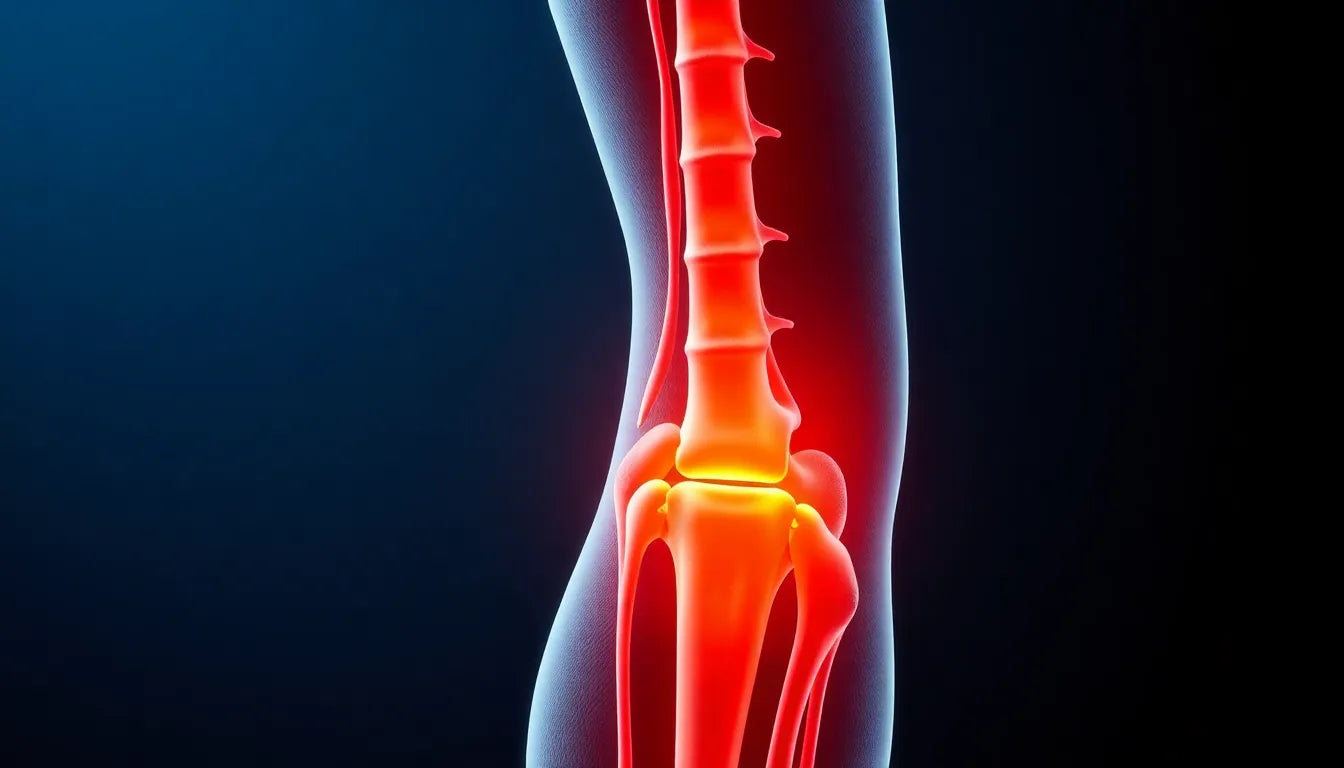

Ontsnap aan de pijn: ontdek hoe je de zenuw van de heup kunt verlichten

Sciatica, veroorzaakt door druk op de nervus ischiadicus, leidt tot pijn van de onderrug naar de voet en beïnvloedt het dagelijks leven. Behandeling combineert fysiotherapie, medicatie en oefeninge...

Sciatische pijn, veroorzaakt door irritatie van de nervus ischiadicus, kan het dagelijks leven aanzienlijk beïnvloeden. Deze blogpost biedt diverse niet-invasieve technieken om de pijn te verlichte...

Sciatique, of ischias, is een pijnlijke aandoening veroorzaakt door druk op de heupzenuw, vaak door een hernia. Symptomen variëren van tintelingen tot ernstige pijn. Deze blogpost biedt een uitgebr...